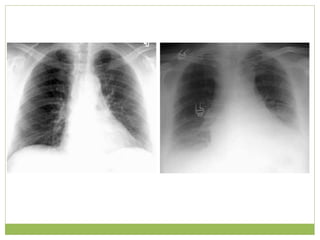

• #7ย This is a PA film on the left compared with a AP supine film on the right.ย ย  The AP shows magnification of the heart and widening of the mediastinum.ย  Whenever possible the patient should be imaged in an upright PA position.ย  AP views are less useful and should be reserved for very ill patients who cannot stand erect. ย  This is a PA film on the left compared with a AP supine film on the right.ย ย  The AP shows magnification of the heart and widening of the mediastinum.ย  Whenever possible the patient should be imaged in an upright PA position.ย  AP views are less useful and should be reserved for very ill patients who cannot stand erect. ย